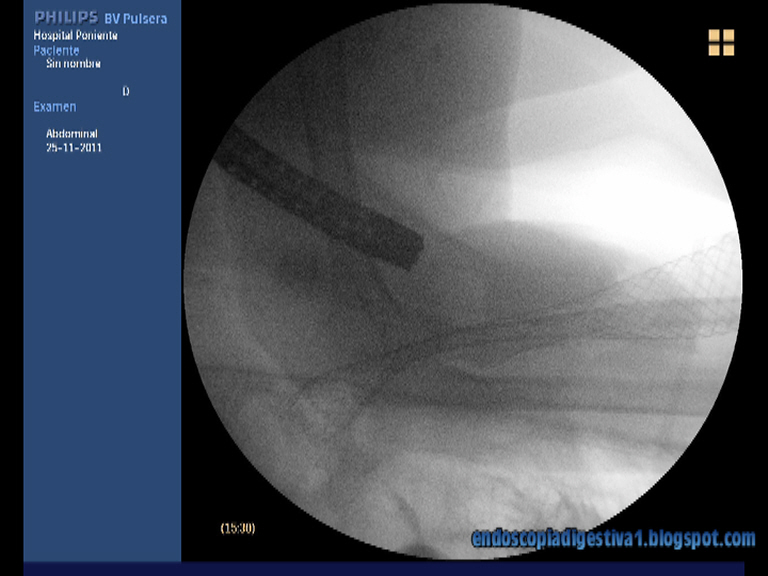

Paciente de 90 años de edad con antecedentes de cardiopatía isquémica, HTA, fibrilación auricular y DM tipo II que ingresa por anemia ferropénica severa (Hb 6.5 gr/dl), cuadro constitucional y vómitos en posos de café de un par de meses de evolución. Se realiza gastroscopia donde se aprecia una estenosis de aspecto neoplásico a nivel prepilórico, que no permite el paso del endoscopio. Las biopsias mostraron un adenocarcinoma gástrico ulcerado, poco diferenciado. El TAC realizado evidenció un engrosamiento de la pared gástrico a nivel antral y prepilórico con infiltarción de la grasa perigástrica y muy probablemente del mesocolon transverso, así como un nódulo de aspecto metástásico en la glándula suprarrenal izquierda (estadio IV). Se decide colocar una prótesis metálica no recubierta paliativa por vía endocópica para garantizar la nutrición de la paciente. Al no disponer en el momento de la colocación de una prótesis Wallflex duodenal, y tener solo Wallflex de colon de 12 cm, se decide usar esta última. Para ello se desenvaina la prótesis del sistema Placehit, se le da la vuelta para que la parte proximal de la prótesis sea la mas ancha y evitar la migración distal una vez colocada en la región antropilórica. La colocación cursa de forma exitosa aunque por su longitud, nos vemos obligados a dejar una mayor parte del stent en la cámara gástrica, pero de forma totalmente funcional.

Dentro de las obstrucciones malignas de la salida gástrica, este caso pertenece a las lesiones de la región antropilórica (mas proximales), generalmente secundarias a adenocarcinomas gástricos. Los otros dos tipos son las localizadas en el área piloro-duodenal y la postbulbar (2ª porción), mas relacionadas con la infiltración duodenal por cáncer de páncreas. En el caso que se expone, hay que intentar colocar la prótesis justo por encima de la papila para evitar la compresión de ésta y por ende la aparición de ictericia. La técnica usada por nosotros es la combinada endoscópico-fluoroscópica. En primer lugar se pasa una guía rígida de 0.035-0.038″ montada en un catéter de CPRE a través de la estenosis. Una vez que haya pasado la guía a las porciones mas distales del duodeno, se inyecta contraste y se mide la estenosis de forma aproximada. Posteriormente se coloca la prótesis sobre la guía. Es muy importante cuando se introduce la prótesis, para evitar perforaciones, traccionar ligeramente de la guía para evitar acodaduras del sistema. Finalmente se libera (sistema de liberación distal) la prótesis, sin prisas, ajustando los extremos (sobre todo distal en este caso). Para esta situación en particular, como se ha comentado anteriormente, al no disponer de Wallflex duodenal y si de colon, dado que son de características similares (en cuanto a material, diámetros proximales, distales, longitudes) y solo diferir en la posición de la parte de mayor calibre para evitar la migración (distal en colon y proximal en duodeno), se decidió desmontar la prótesis del sistema de liberación, darle la vuelta y con paciencia y algo de maña, montarla de nuevo.